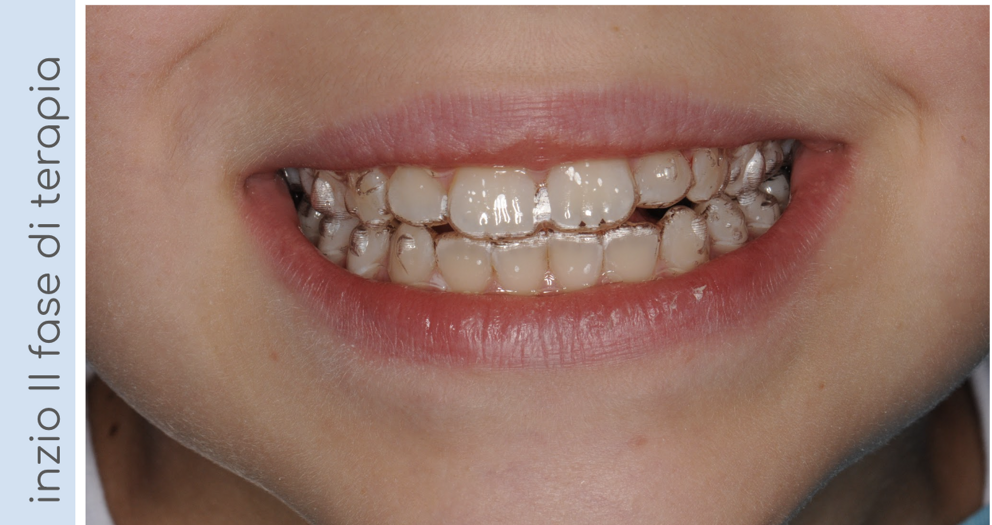

In questo caso, il paziente presentava un morso crociato posteriore a sinistra, intercettato precocemente e corretto in dentatura mista. Al termine della terapia intercettiva, una volta erotti tutti i denti permanenti, il nostro piccolo paziente ha iniziato una seconda fase di terapia con allineatori trasparenti per finalizzare il trattamento e allineare correttamente le arcate!